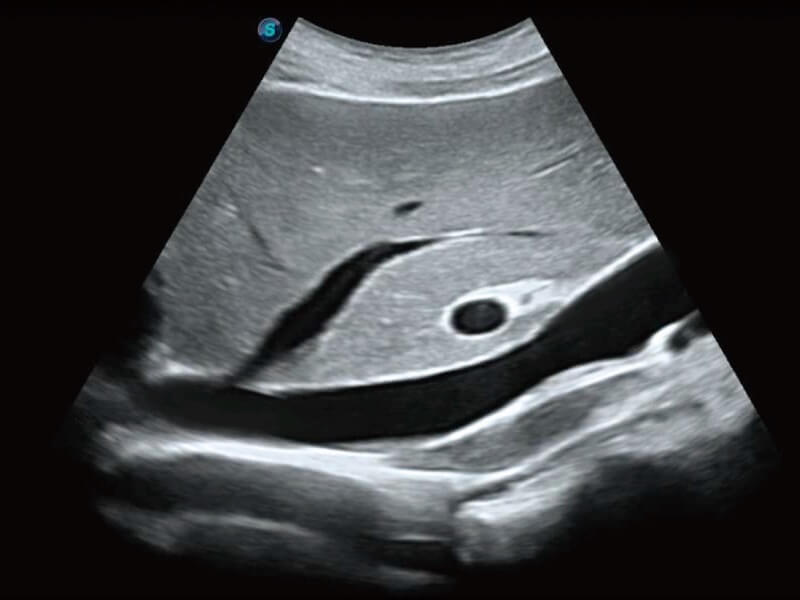

Die Bildqualität liegt immer im Zentrum definierter klinischer Ergebnisse. ELITE liefert eine leistungsstarke und klare Bildgebung, die durch eine leistungsstarke Architektur, hochmoderne Sonden und ausgeklügelte Verarbeitungsalgorithmen erzeugt wird, für ein höheres Maß an Klarheit und Vertrauen.

Basierend auf einem verlässlichen Deep-Learning-Algorithmus für Big Data ist S-Fetus eine brillante Komplettlösung für automatische Standard-Ebenen-Erfassung und Messung. Mit nur einem Klick werden gängige fetale Biometrie-Ergebnisse mit hoher Intelligenz, Genauigkeit und Effizienz erzielt, um einen beispiellosen Bedienungskomfort zu gewährleisten.

Dank der Unterstützung von Auto OB wird eine schnelle und hoch effiziente fetale Biometrie erreicht. Gleichzeitig kann diese auf Deep Learning basierende Methode zu konsistenteren Ergebnissen führen und die Variabilität, die vom Anwender abhängig ist, effektiv reduzieren.

Ultraschall wird immer vielseitiger und übernimmt immer mehr klinische Aufgaben. Als Vorreiter, der Ärzten dabei hilft, mehr zu erreichen, ist ELITE mit einer umfassenden Palette fortschrittlicher Funktionen für die Allgemeine Bildgebung, Gynäkologie/Geburtshilfe, Kardiologie und mehr integriert.

Ultraschall wird immer vielseitiger und übernimmt immer mehr klinische Aufgaben. Als Vorreiter hilft ELITE den Ärzten dabei, mehr zu erreichen, indem es mit einer umfassenden Palette fortschrittlicher Funktionen ausgestattet ist, die die allgemeine Bildgebung, die Geburtshilfe/Gynäkologie, die Kardiologie und vieles mehr abdecken.